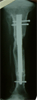

Post

Op

Intramedullary lengthening with Fitbone system and Osteotomy at 2nd level to correct procurvatum

Lengthening of bone and distal osteotomy uniting